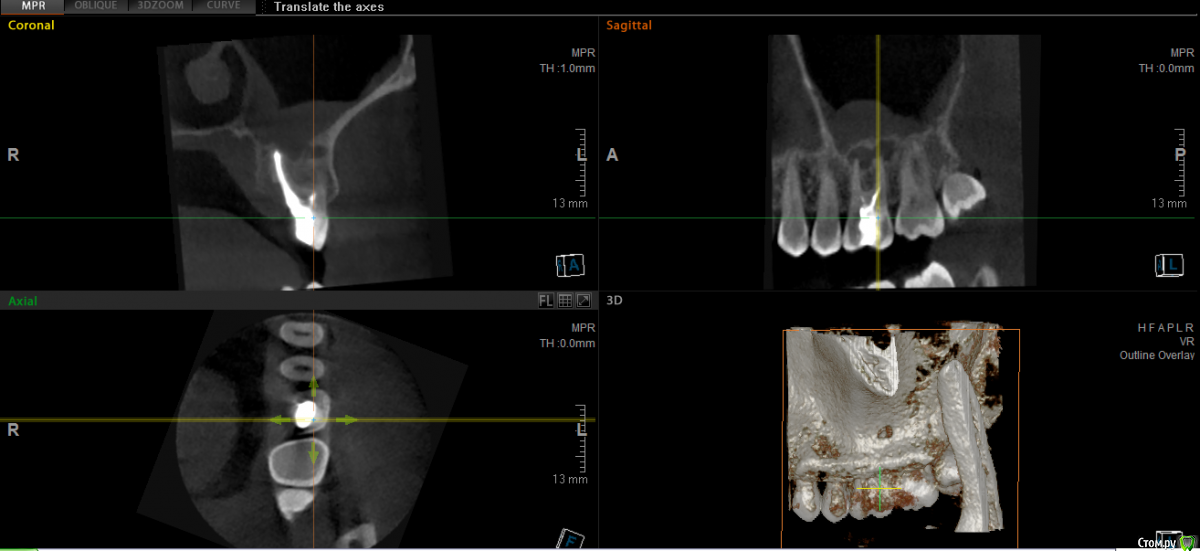

major Опубликовано 1 октября, 2015 Поделиться Опубликовано 1 октября, 2015 КТ посмотрел.Удалять, с последующей имплантацией и протезированием. Слишком глубокий скол. Ссылка на комментарий

Евгений+ Опубликовано 1 октября, 2015 Автор Поделиться Опубликовано 1 октября, 2015 (изменено) Можно несколько вопросов по имплантации: 1. Возможна ли одномоментно с удалением?2. Какая сейчас толщина кости до пазухи? (хватит для имплантата или нужно наращивать кость)3. Будет ли влиять на имплантацию гранулема/киста или сначала с ней нужно разобраться?4. С удалением нужно поторопиться или желательно что бы кто удалял тот и ставил имплант? Спасибо! Изменено 1 октября, 2015 пользователем Евгений+ Ссылка на комментарий

колесников Опубликовано 1 октября, 2015 Поделиться Опубликовано 1 октября, 2015 У вас там на 3ёх корнях по кистогранулёме и полип в пазухе. Дно пазухи перфорировано ,корни и что неприятно,корневой наполнитель контактируют с полипом. Сохранять нельзя-удалять. Обратитесь к отоларингологу,эндоскопически желательно исследовать полип. Если просто пролиферация интимы-можно удалять и ставить имплант одномоментно,если это грибковый полип-вначале удаляете зуб и полип ,а только затем решаете вопрос с пластикой. Ссылка на комментарий

Евгений+ Опубликовано 5 октября, 2015 Автор Поделиться Опубликовано 5 октября, 2015 У вас там на 3ёх корнях по кистогранулёме и полип в пазухе. Дно пазухи перфорировано ,корни и что неприятно,корневой наполнитель контактируют с полипом. Сохранять нельзя-удалять. Обратитесь к отоларингологу,эндоскопически желательно исследовать полип. Если просто пролиферация интимы-можно удалять и ставить имплант одномоментно,если это грибковый полип-вначале удаляете зуб и полип ,а только затем решаете вопрос с пластикой. Спасибо большое за рекомендации. Сходил у лору, он посмотрел КТ и сказал что это воспаление слизистой пазухи только над больным зубом, из-за кисты (не гайморит и не полип). Подскажите, что должен сделать врач или на что нужно обратить внимание, в случае перфорации пазухи со стороны корней? Я так понял там могут быть отверстия? Ссылка на комментарий

колесников Опубликовано 5 октября, 2015 Поделиться Опубликовано 5 октября, 2015 Сходил у лору, он посмотрел КТ и сказал что это воспаление слизистой пазухи только над больным зубом, из-за кисты (не гайморит и не полип).Изменение (утолщение,воспаление,разрастание) слизистой пазухи,уже является гайморитом,в данном случае хроническим и одонтогенным. Отверстия там конечно есть,но перфорации не будет,отёкшая слизистая всё затампонирует. Как быть с лункой-доктор знает,положитесь на его умение. Ссылка на комментарий